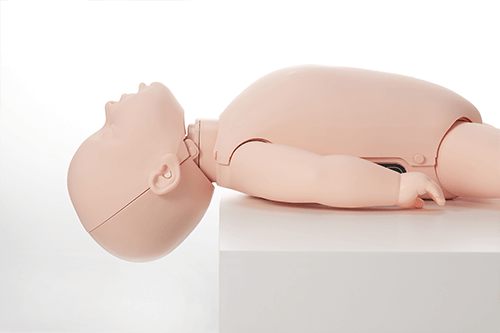

- The Brayden Baby has a realistically large occiput so the Baby lies with its head in a realistic position (in flexion).

- The head needs to be moved to open the airway in to a neutral position.

- Correct positioning of the head into the neutral position to open the airway.

- Realistic occlusion of the airway for an infant when the head is hyperextended.